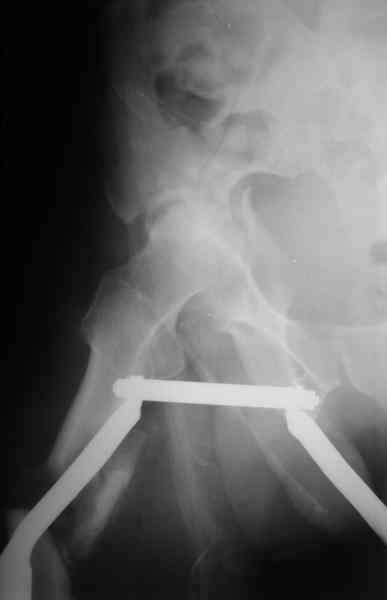

Здравствуйте Анатолий Федорович. Сегодня заситезировали этопу пациенту длинные трубчатые кости. В отношении вертлуги мы остановились на остеосинтезе вертлужной впадины из доступа Кохер -Лангенбек. Необходимость (и возможность) закрытого вправленя через месяц представляется сомнительной - даже если удастся - судьбу головки

это вряд ли изменит в лучшую сторону, а если вправить, то на нее будет осуществляться давление отломком,связанным с осевым скелетом. В дальнейшем, если возникнут ожидаемые проблемы с АНГБ, коксартрозом, вернямся к этому больному. (описанную вами операцию надо хоть посмотреть разок, наверняка есть какие-нибудь тонкости).